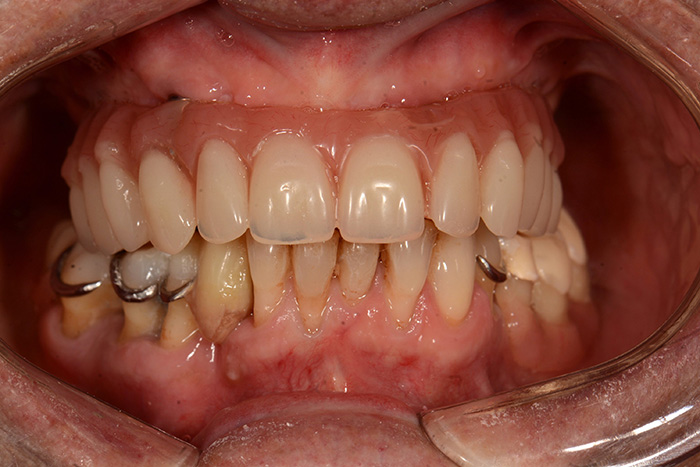

Fig. 13 : Des composites ont été réalisés en bouche au niveau de 44 et 45 pour retrouver des contacts lors de l’occlusion en intercuspidie maximale et en fonction de groupe lors de l’occlusion fonctionnelle droite.

Fig. 14 : Latéralité gauche en fonction de groupe.

Fig. 15 : Latéralité droite en fonction de groupe.

Nous retrouvons des AFMP droit et gauche symétriques, ce qui permettra une mastication unilatérale alternée.